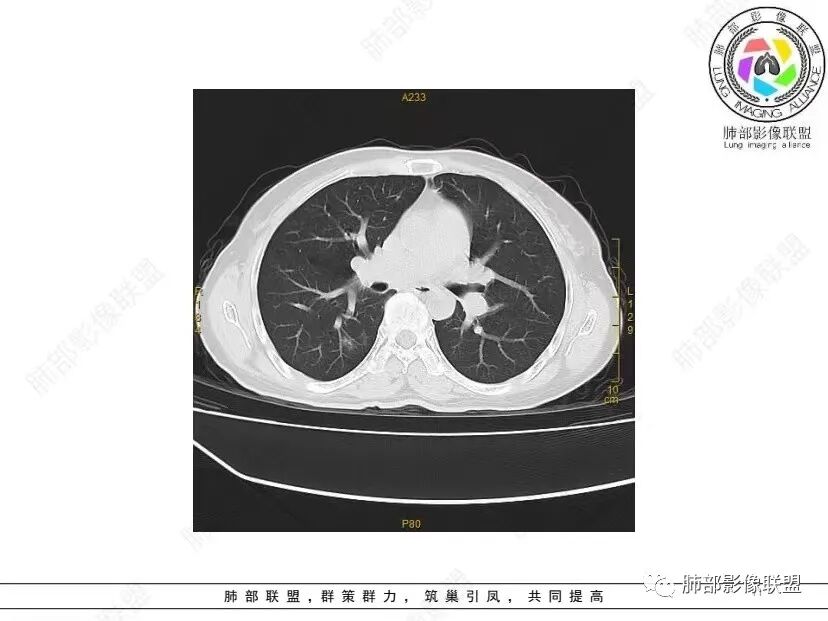

中年女性,否认肿瘤病史,双肺多发气囊,中下肺相对多发,考虑LIP,鉴别BHD综合征。

秦化君: 晨读 双肺不均匀散在多发囊状影,大小不等,部分囊形态欠规整,壁薄均匀,部分囊胸膜下平行。双肺少许斑片状磨玻璃影,边缘模糊。考虑BHD综合征。鉴别PCP,LIP。

红日初升: 中年女性,双肺多发气囊,背景干净,大小不一,下肺韧带旁较大,考虑BHD,鉴别LIP、LAM

玫: 晨读:女,49岁,双肺散在多发囊性病灶影,薄壁,部分层面病灶形态欠规整,右肺下叶少许磨玻璃影,边缘模糊,考虑LIP,鉴别BHD。

宇宙: 中年女性,两肺多发大小不等薄壁囊状影,两肺纵膈胸膜下分布明显,考虑BHD,鉴别LAM

放射线 (王秀仙): 双肺多发囊状影,大小不等,部分囊壁呈磨玻璃样,另双肺见斑片状磨玻璃影,边缘模糊。女性,考虑LIP,鉴别BHD

段建民: 双肺多发囊状影,多成圆形或三角形,囊壁薄且均匀,正常肺野内透过度尚可。双肺多发囊状影的鉴别,中心肺气肿,间隔旁肺气肿,PJP,支气管扩张,囊肿,支气管肺发育异常;LAM LIP PLCH BHD;囊腔腺癌,转移瘤,血播金葡菌……

本病例首先考虑BHD。

良孑: 两肺多发含气囊腔,大小不等,囊周见血管伴行,首选BHD,建议查双肾情况,鉴别Lam

这个病例目前影像特点,多囊,囊主要位于下肺,胸膜下及小叶核心为主

伴随少许索条,而且这些病灶与囊不一定有相关性

囊的分布,PLCH基本可以排除

囊壁薄且均匀,光滑,形态规则,基本除外恶性

单纯囊,无斑片及其他实性病灶,感染不支持,可能的是:LAM、BHD、LIP

从囊的分布、大小,BHD可能性可能大一些,但是LIP、LAM都可以这样表现,具体诊断应该是这三种之一,影像缩小到这里我觉得就差不多了,结合临床考虑就行,不支持靠影像强下结论。

临床诊断BHD综合征需要满足一个主要或两个次要标准。主要标准包括:1、皮肤上至少发现5个纤维滤泡瘤,至少1个组织学证实;2、致病的FLCN种系突变阳性。次要标准:1、多发肺囊肿,双侧基底部,有或无自发性气胸;2、肾癌,起病早(<50岁)或多灶性或双侧;3、 BHD综合征一级亲属。BHD主要影像表现特征:1、两肺内肺囊肿:80%以上的BHD患者会出现肺内囊肿,且倾向于基底部近胸膜下分布,特别是纵隔侧肺膜下,囊肿形状不规则、囊肿可大可小,肺内囊肿多毗邻肺下动脉或静脉近端,胸部CT上囊肿分布和特点对诊断有提示意义。2、继发自发性气胸:BHD患者发生气胸风险是正常人的5倍,BHD患者的气胸发生率约为1/4,气胸复发率则高达59%。3、肾肿瘤:(常为双侧性、倾向于嫌色细胞组织学亚型)4、皮肤表现:(为面、颈部纤维性毛囊瘤、毛盘瘤)